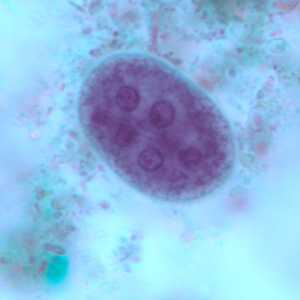

E. polecki cysts stained with trichrome.

Figure A: Cyst of E. polecki stained with trichrome. Notice the large nucleus with a pleomorphic karyosome and numerous variably-shaped chromatoid bodies.